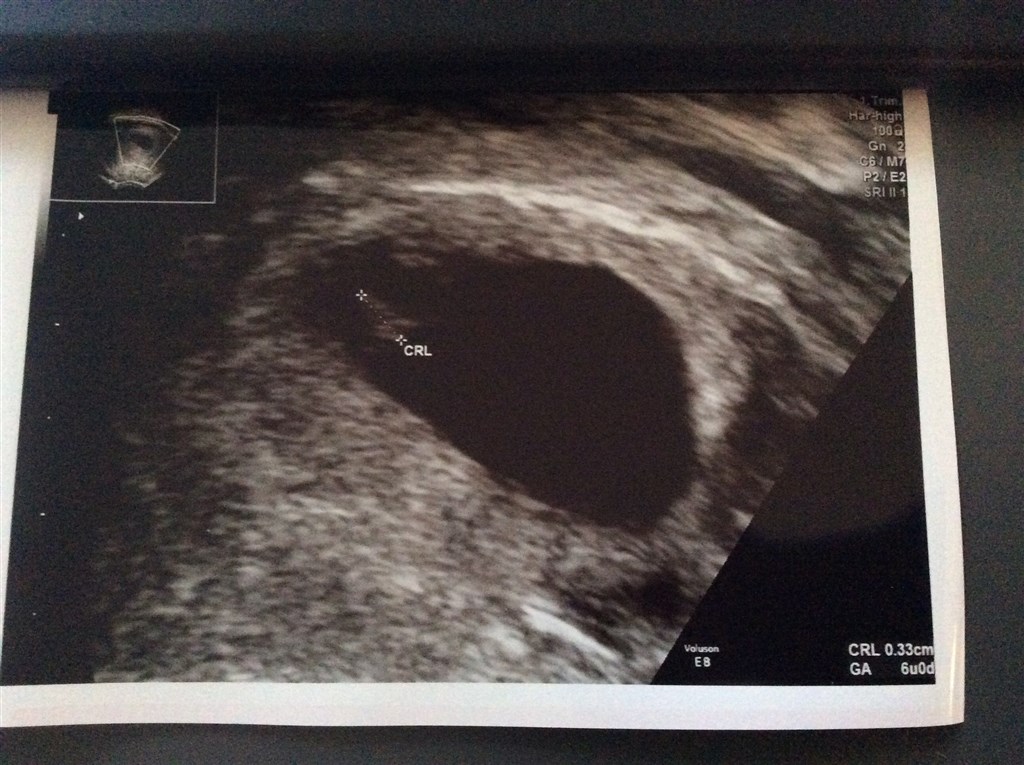

Jeg testede MEGET positiv i lørdags, og var usikker på om jeg var 5 eller 6 uger henne, så tog en tidlig scanning i dag, bare for at vide hvor langt jeg var.. Der var en fin lille reje, med meget flot hjerteblink og de mente jeg var 6+0 ( sådan cirka )

Og så et billede af "noget" fra uge 6+0